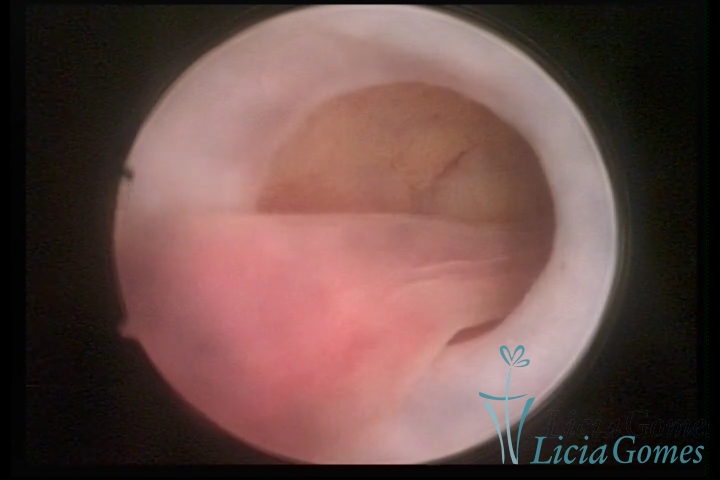

PÓLIPOS ENDOCERVICAIS

São tumores benignos, resultantes da proliferação focal reativa aos processos inflamatórios ou à situações de hiperestrogenismo, e podem ter sésseis (com a base de implantação larga) ou pediculados do epitélio.